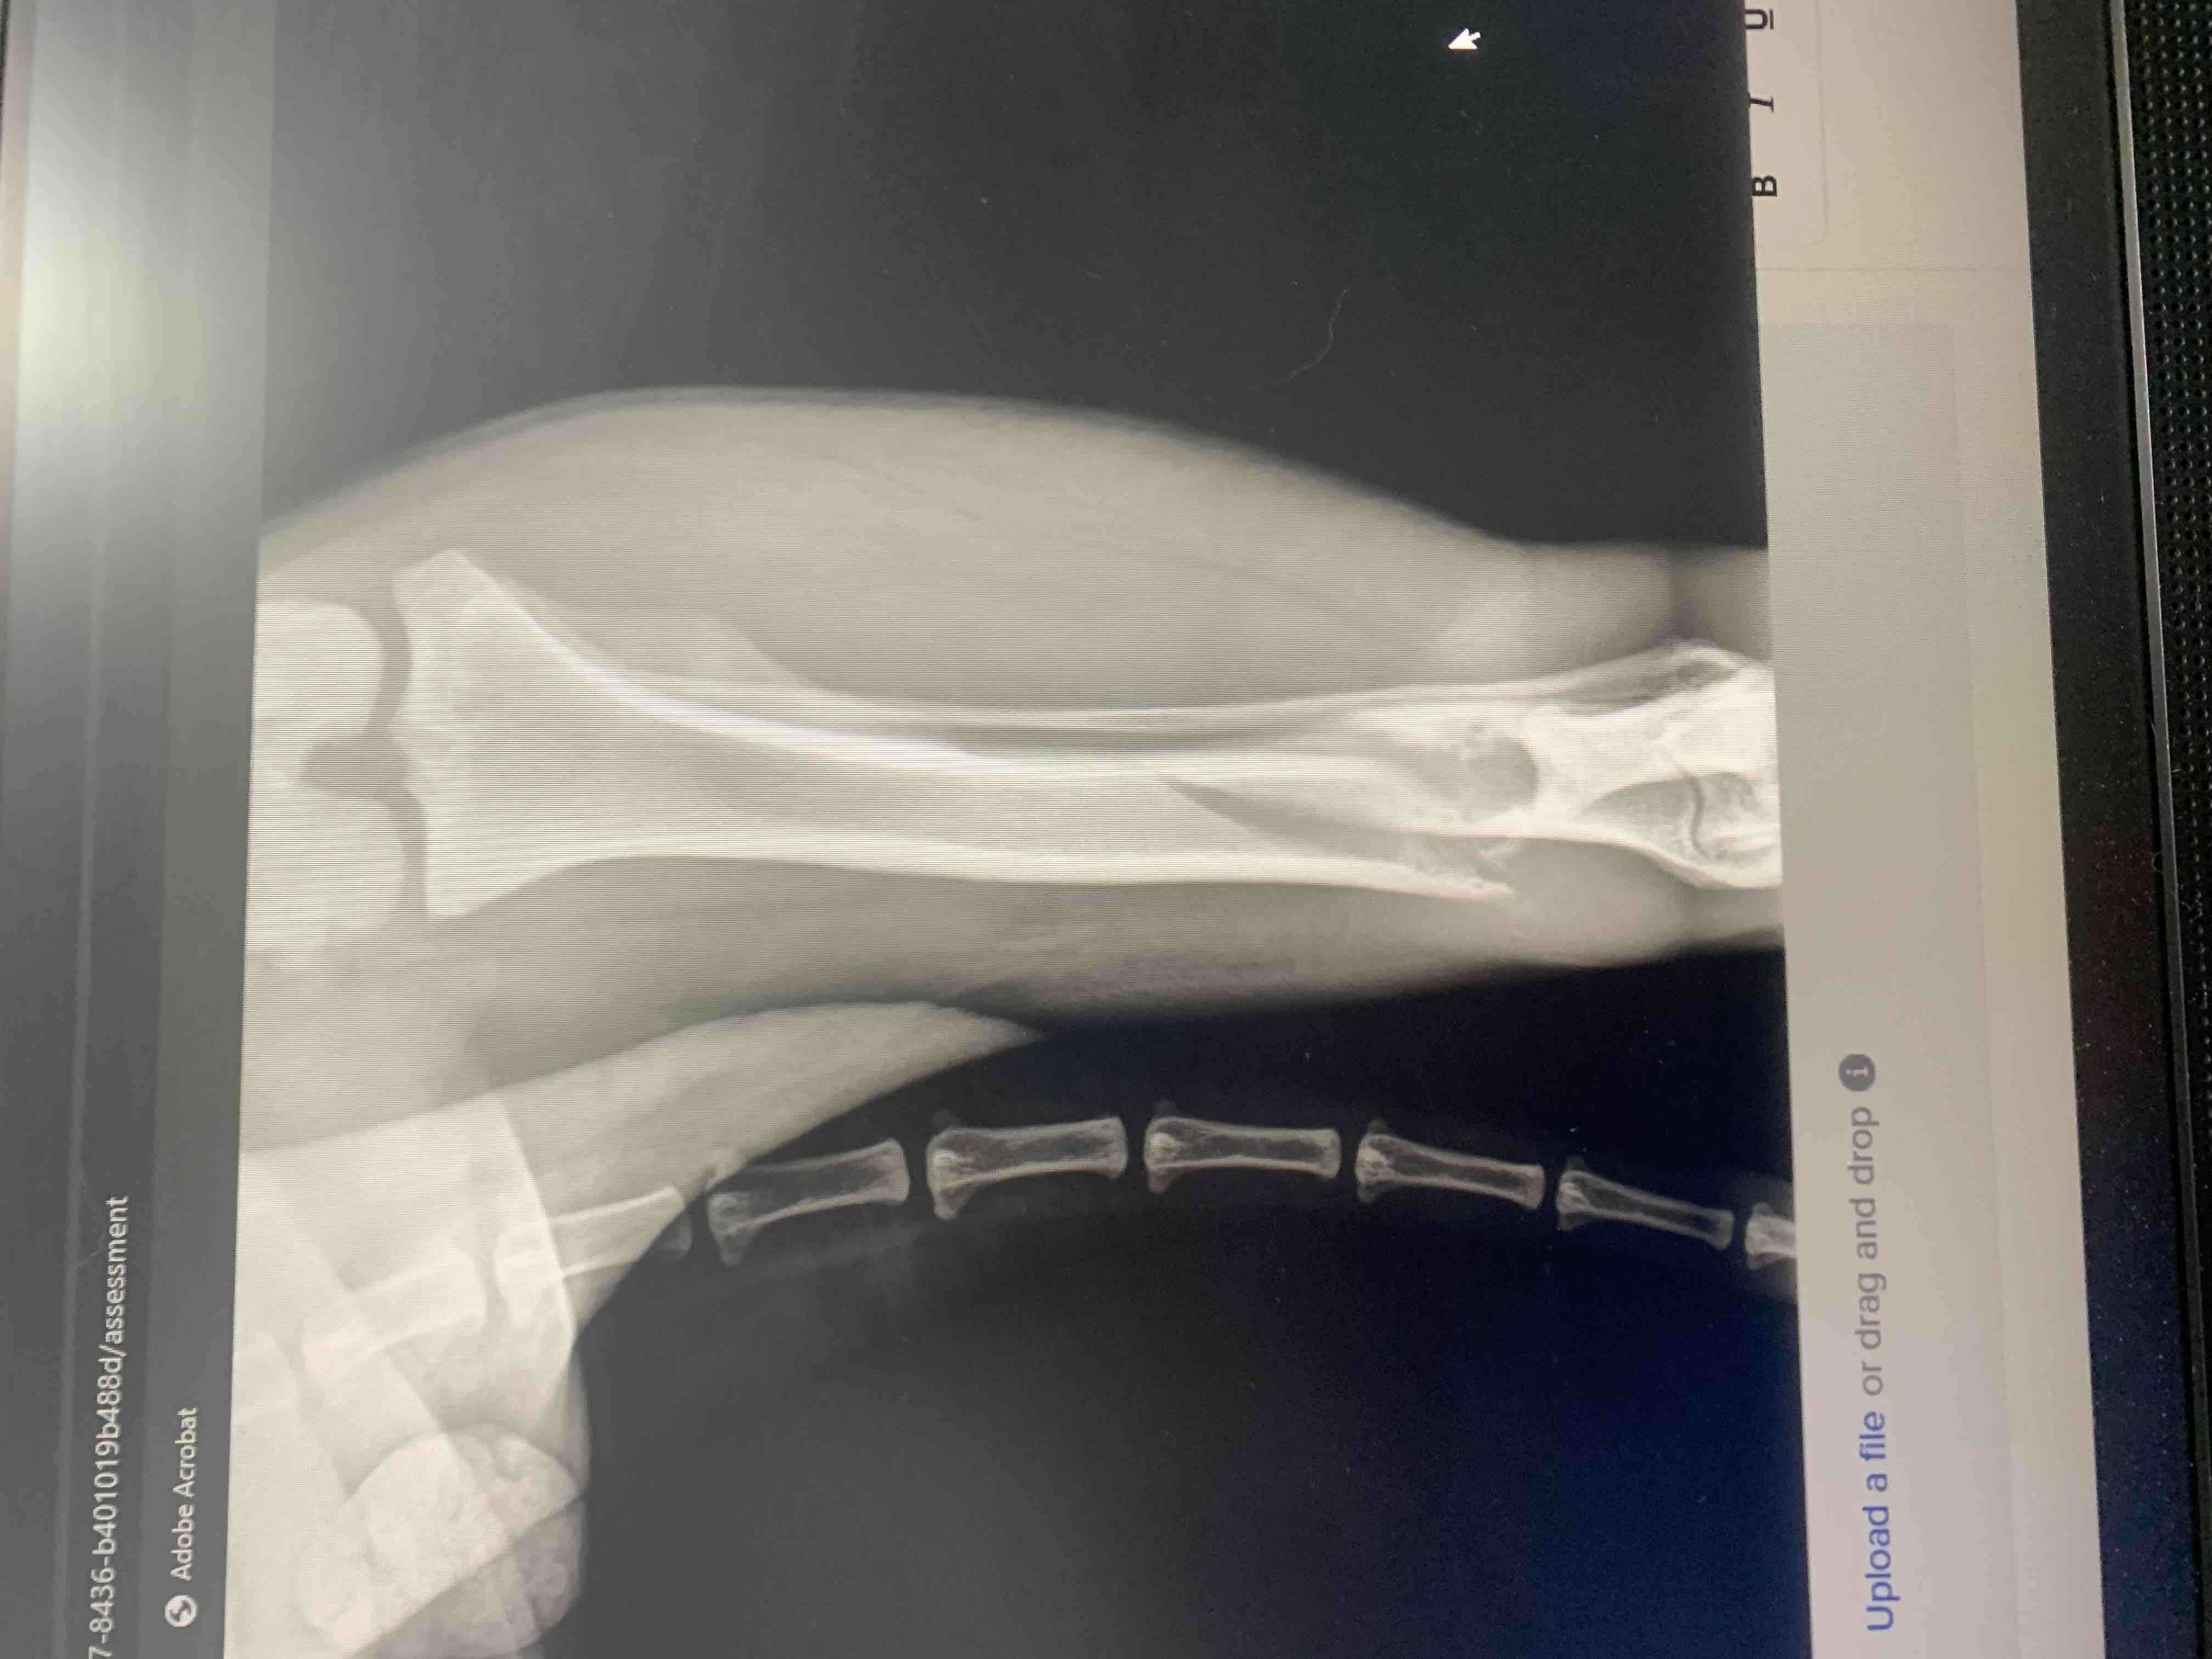

Mac has been a beloved part of our family since he was a puppy. He’s always been full of energy and love, bringing so much joy to our lives every single day. Recently, our world was turned upside down when Mac fractured his leg. After taking him to the vet, we received the heartbreaking news that he also has cancer. The doctors have told us that Mac will most likely need to have his leg removed to give him the best chance at recovery.